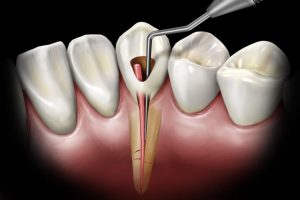

En quoi consiste le traitement endodontique ?

Le traitement endodontique est une procédure clinique qui va permettre d’augmenter les chances de conserver les dents, il a un très haut niveau de succès. Cependant, cette thérapeutique reste une procédure biologique, et comme tout autre acte médical, le succès ne peut pas être garanti à 100%.